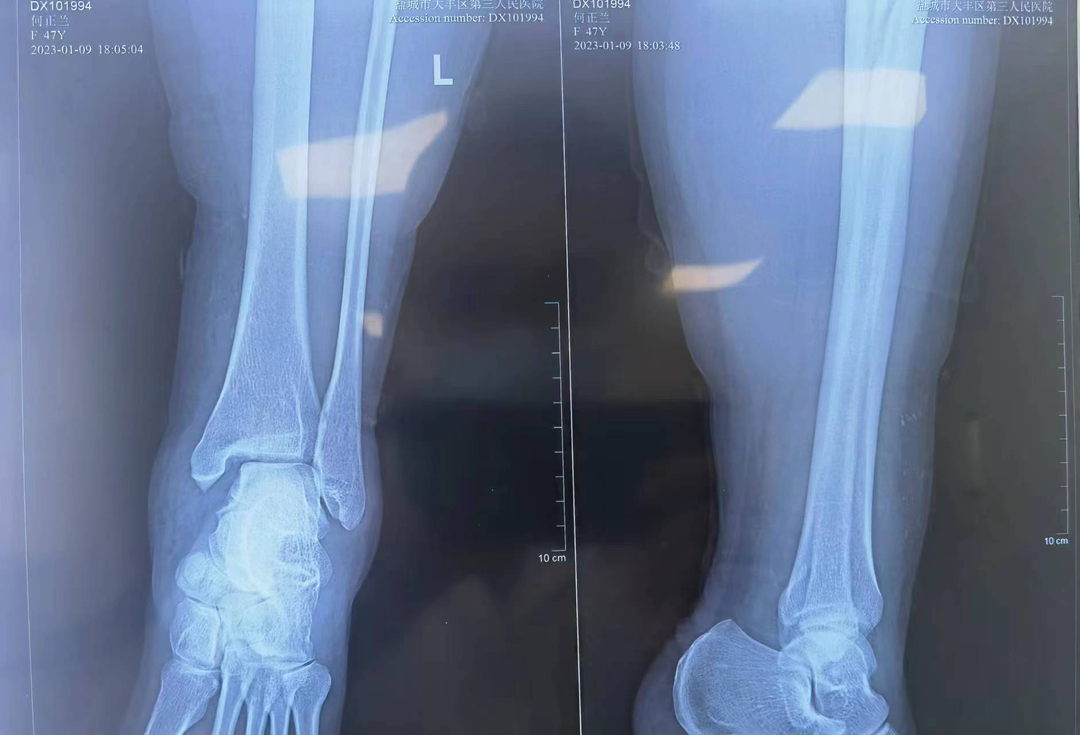

近日,我院急诊收治一名踝关节扭伤病人,患者女性,47岁,就诊时踝关节肿胀较严重,疼痛剧烈,活动受限,查体因疼痛不能完成。 急诊踝关节摄片提示:左踝关节脱位。当晚值班医师立即汇报骨科梁永新主任,根据患者扭伤机制,梁主任指示该患者为一种特殊类型的踝关节骨折(Maisonneuve骨折)。此类病例极易漏诊,患者常合并有腓骨近端骨折、后踝骨折、下胫腓前韧带损伤、三角韧带损伤。需立即完善膝关节DR检查及踝关节三维重建CT。 (术前DR) 明确并支持诊断,向患者交代病情,因患者日常活动量较大,需手术治疗完全纠正踝关节脱位,并对踝关节下胫腓前韧带、内踝三角韧带进行修补。修补后的韧带强度远大于疤痕愈合的强度,能最大程度减轻或避免踝关节创伤性关节炎的发生,患者考虑后表示同意,立即办理入院手续。 入院后,梁永新主任对其予以下肢石膏托中立位外固定、冰敷、改善血液循环、止痛等对症处理。第5天,梁主任经过术前充分评估,同患者及其家属充分沟通后,协同麻醉科沈智勇主任,骨科团队单金平、周奇凡医师共同完成手术。术中探查后发现与术前诊断完全一致,予以逐一修补,术中摄片提示踝关节脱位完全纠正,手术过程十分顺利。患者术后第2天,在陈锡丰护士长率领的护理团队的精心指导下下床不负重活动。术后1周办理出院,患者对于手术效果非常满意。 (术后复查DR、CT) (术后三天伤口) 梁永新个人简介 梁永新,中共党员,硕士研究生,副主任医师,2003年毕业于新疆医科大学临床医学院,2009年于新疆医科大学取得肿瘤学硕士学位,现任盐城市大丰区第三人民医院骨科主任,乌鲁木齐市工伤鉴定专家组成员。 从事骨科临床及相关研究工作17年,并长期开展规培生授课、带教、乌鲁木齐市级工伤鉴定等工作。擅长骨与关节、运动医学、创伤、脊柱退行性疾病、小儿骨科的诊治,主要开展肩、膝、踝关节镜、关节置换、创伤、脊柱、小儿骨科等手术。 读研期间在新疆维吾尔自治区人民医院骨科学习创伤骨科、新疆医科大学附属肿瘤医院学习骨肿瘤诊治;工作期间曾赴广东省人民医院骨科进修学习关节与运动医学;硕士研究生毕业后曾在乌鲁木齐市友谊医院骨科、乌鲁木齐市第一人民医院骨科等三甲医院工作。 在国家级核心期刊发表论文3篇(第一作者),省级核心期刊发表论文5篇(第一作者),出版骨科专著1本(副主编),取得国家级实用型专利1项,参与完成乌鲁木齐市级科研课题1项。